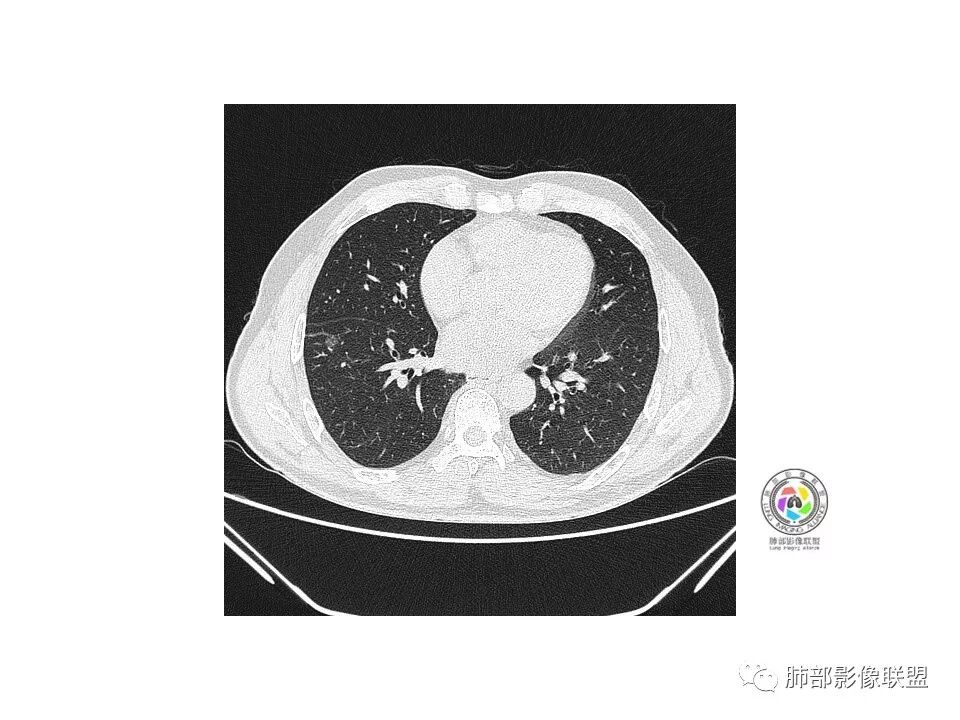

右肺下叶见边界清晰混合磨玻璃密度影,目测内见实性结节小于5mm,有浅分叶,前缘小叶间隔阻挡,月牙铲?胸膜牵拉,老年患者,MIA可能,鉴别炎性病变,抗炎后复查

患者老年男性,以咳嗽 、咳痰3天就诊,胸CT:右肺下叶前基底段mGGO,内可见血管形态改变,细支气管扩张,病灶边界清,边缘可见月牙铲。考虑恶性,腺癌?但建议先抗炎治疗后复查

老年男性、咳嗽咳痰三天,右下前基底段GGN,血管影增多,伴类似的树芽,边缘稍模糊,考虑结核。

右肺下叶磨玻璃结节,密度不均,边缘收缩,胸膜牵拉,考虑炎性,建议复查,除外腺癌。

右肺下叶混合磨玻璃结节,边缘清晰,浅分叶,月牙铲,胸膜牵拉,血管进入,考虑MIA可能,鉴别炎性病变

磨玻璃结节,边缘清楚,浅分叶,月牙铲,考虑腺癌可能,抗炎后复查。

右肺下叶混合磨玻璃密度结节影,局部胸膜牵拉,月牙铲,考虑腺癌

磨玻璃小结节,有明显收缩性表现,胸膜凹陷,考虑腺癌

患者老年男性,咳嗽  咳痰3天就诊。胸部CT:右肺下叶前基底段混合磨玻璃结节,边缘清楚,可见毛刺、胸膜牵拉、血管集束、月牙铲征象。综合考虑微浸润腺癌可能大。

右肺下叶前基底段混合磨玻璃结节,边界清,浅分叶,胸膜牵拉,月牙铲,血管进入,考虑:微浸润腺癌可能性大,抗炎后复查。